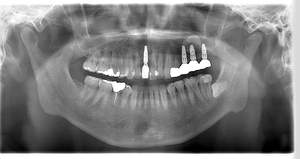

レントゲン写真

- Befor

- After

| 年齢 | 50代・男性 |

| 主訴 | 左上7番 左下5番7番 |

| 治療内容 | ・インプラント埋入 ※1:GBR(骨造成)・・・骨再生誘導法。骨の高さや厚みを人工骨や人工膜などを使用し再生する方法 |

| 治療費 | 合計:1,809,500円(税込) ■内訳 ・左上7番 ・左下5番7番 |

| 治療期間 | 左上7番約1年 左下5番7番約10ヵ月 |

| 治療方針 | 左上7番は昔他院で被せものをしており、被せものの中が歯ぐきの中まで虫歯になっていたため抜歯せざるを得ない状態だった。抜歯と同時に骨造成を行い、骨が出来るまで4ヵ月待ってからインプラントを埋入した。 ※2ポンティック・・・歯のない部分を補うダミーの歯。 |

| 担当者所見 | 元々金属の被せものが多く入っていたため、2次カリエス※3が多かった。今回は金属ではなく、ジルコニアを使用し、2次カリエスにならないよう、患者様にはブラッシング指導とメンテナンスの重要性をお伝えした。 ※3二次カリエス・・・詰め物や被せものを入れた歯が虫歯になること。 |